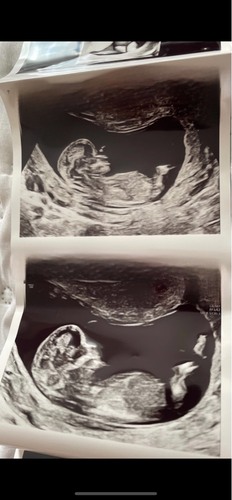

Ah kijk nu snap ik hem denk ik🙈 precies 13 weken. Hoop dat deze goed is om ...

Deze is wel erg vaag. En de blaas lijkt niet vol en niet goed te zien.

Maar ik gok een meissie 💕